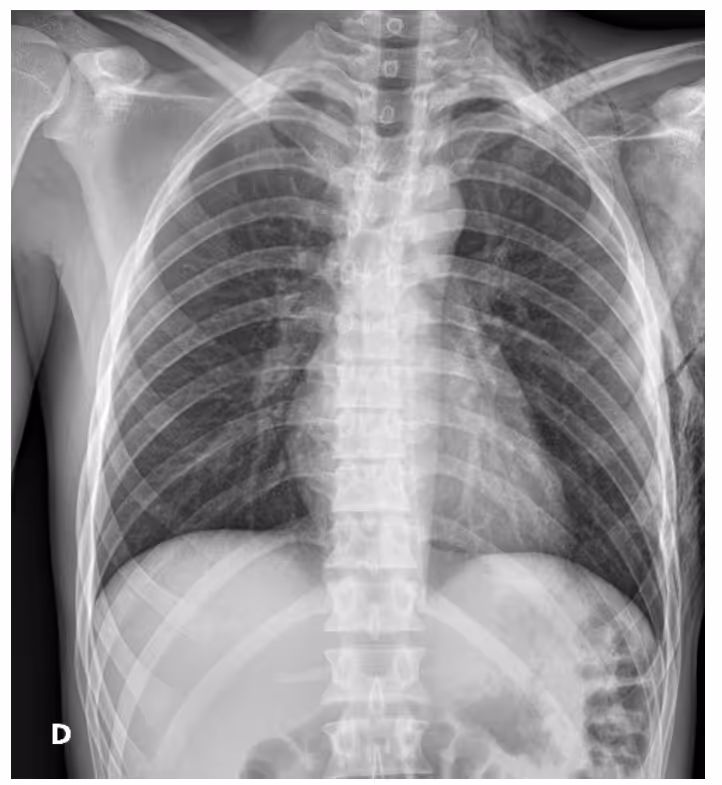

To prevent quick progression of small pneumothorax to a large-size pneumothorax, chest x-rays must be repeated within 3-6 hours after admission for patients on observation. Spontaneous hemopneumothorax must be considered during this period. Imaging evaluation should be done within 12-48 hours after discharge. Admission observation is recommended for patients without reliable follow-ups to prevent the condition from worsening.

DrAid for Pneumothorax helps to compare side-by-side images for follow-up in pneumothorax patients. This aided reading allows doctors to create a suitable treatment plan for the patient.Interested in deploying DrAid at your health facility?